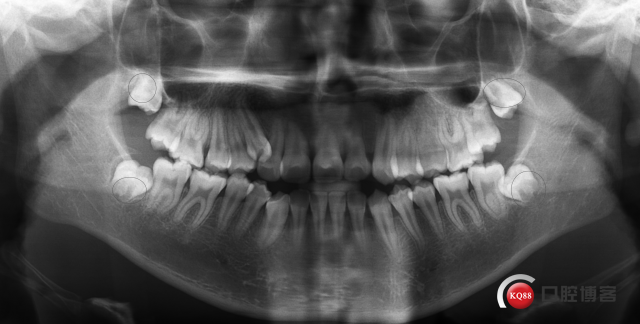

初诊全景片:智齿牙胚存,38,48牙冠基本发育正常,位置较正,髁突右侧略大于左侧,下颌升支无明显不对称。

牙型:安氏Ⅲ类错合;

骨型:一类高角,下颌发育过度,下切牙代偿性舌倾